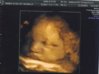

A to zdjecie z wczorejszego USG 35 tydzien waga 2392g

001.jpg